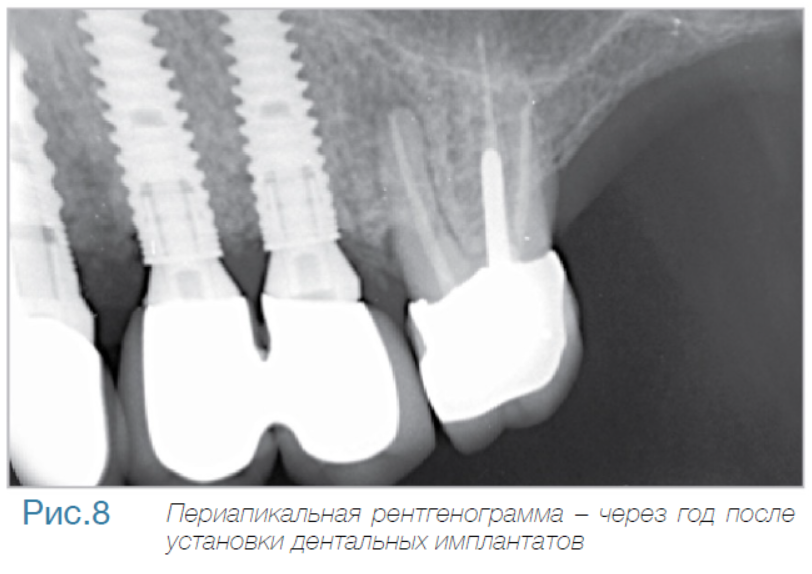

В частной практике (LS) были установлены 30 имплантатов MIS С1 (конических, с внутренним коническим соединением с переключением платформ). В исследовании приняли участие 10 мужчин и 8 женщин, при этом средний возраст пациентов составил 57 лет (возрастной диапазон 35-75 лет). 6 пациентов были курильщиками. 9 имплантатов установили на верхней челюсти, 21 – на нижней челюсти, 13 – во фронтальной области, 17 — в области боковых зубов. Для 10 имплантатов был использован одноэтапный протокол имплантации, для 20 — двухэтапный. Керамические реставрации были зафиксированы на имплантатах через 3 (18) и 6 (12) месяцев после их установки. Уровень маргинальной костной ткани с мезиальной и дистальной сторон имплантатов измерили с помощью рентгенограмм непосредственно в день установки дентальных имплантатов (исходный уровень), в день раскрытия (через 3 или 6 месяцев после установки) и ровно через год после проведения дентальной имплантации.

Ни один из имплантатов не был утрачен в течение первого года после установки, что означает 100% уровень приживаемости по прошествии года. Сокращение маргинальной кости за этот промежуток времени от имплантата до крестальной кости составило 0.7 ± 0.47 мм. Так же отсутствовала разница в сокращении уровня маргинальной кости между имплантатами, установленными по одноэтапному и двухэтапному протоколам.